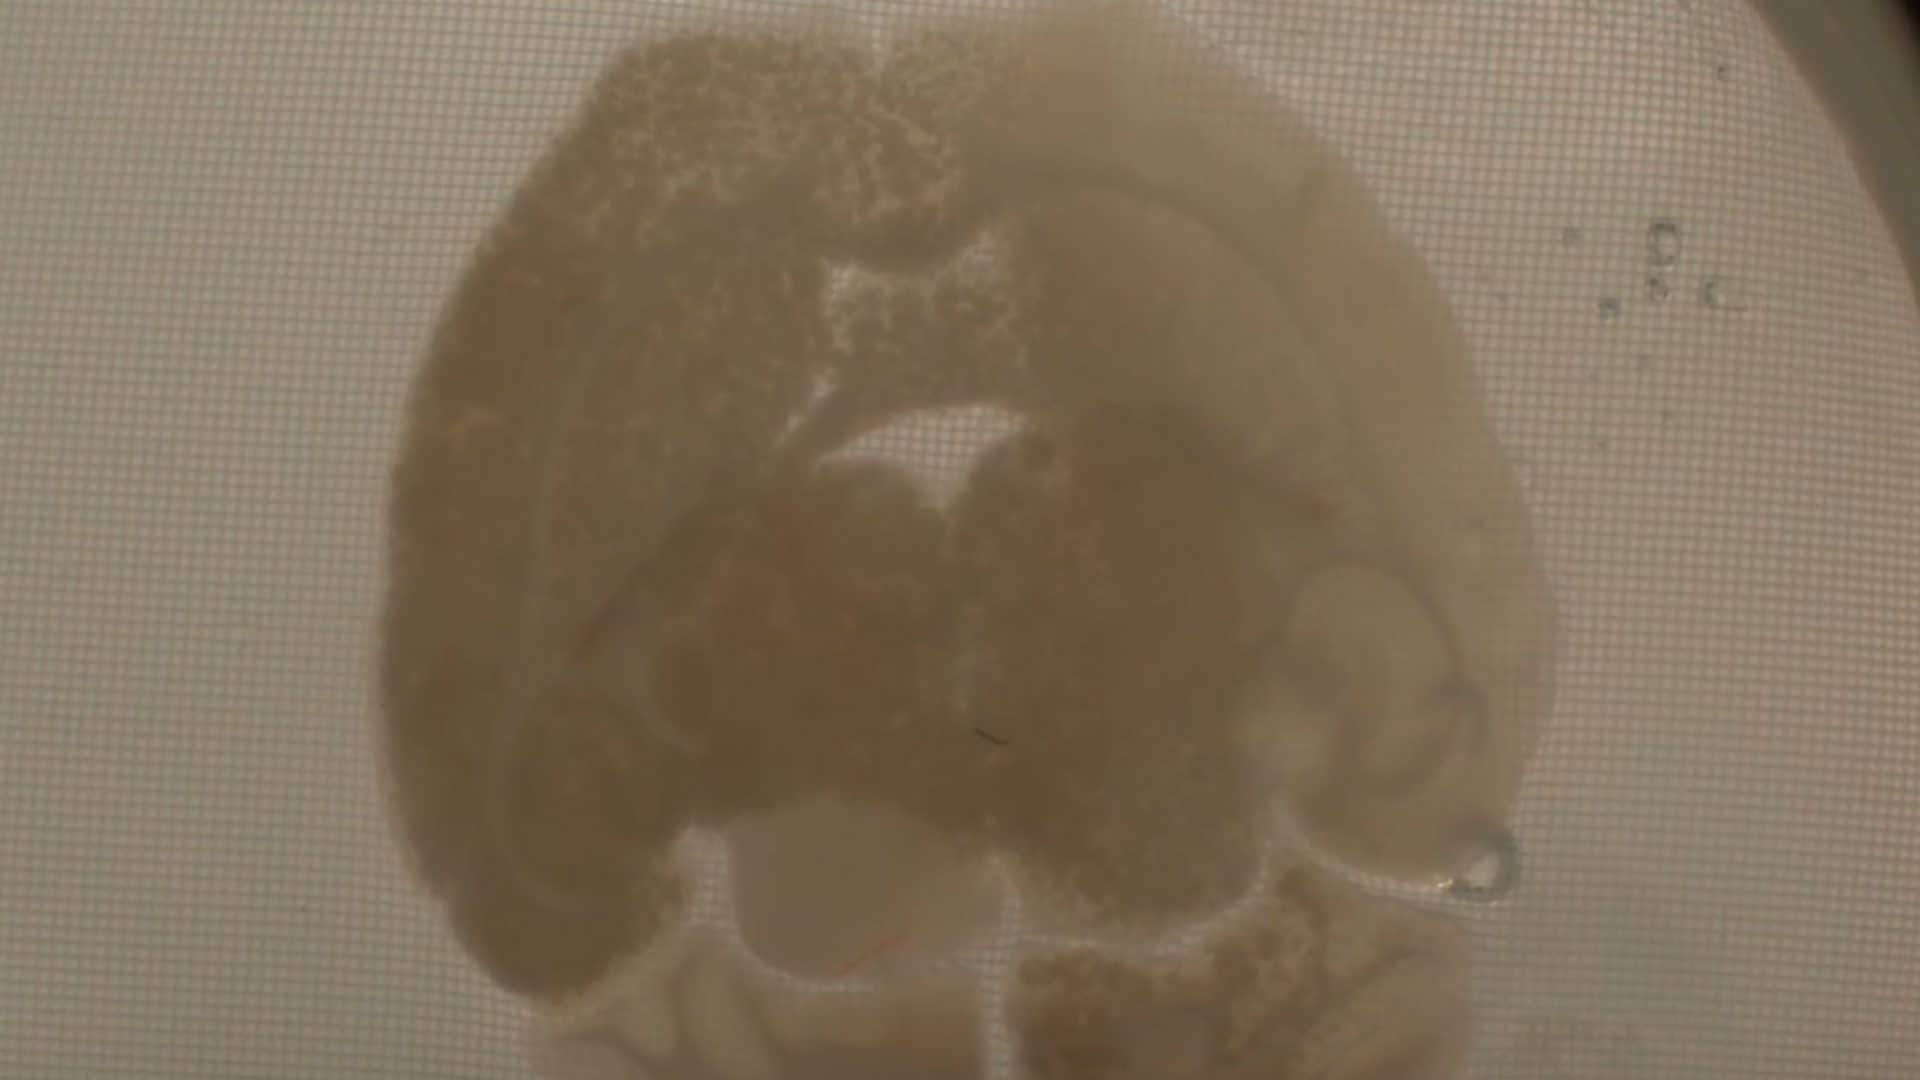

Ecco il primo cervello criopreservato senza danni

I ricercatori sono riusciti ad ibernare (criopreservare) e a riportare in temperatura un cervello di coniglio senza danneggiarlo. Si tratta di un grande passo in avanti nel campo della crioconservazione.Credit: https://spaces.hightail.com/space/nG6KQ